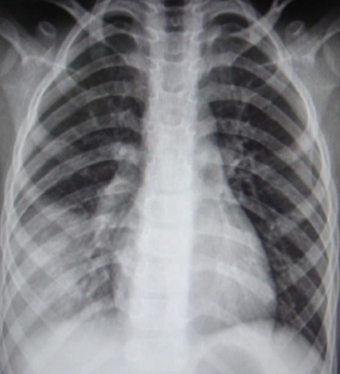

3.影像学检查:胸部X线和CT检查是诊断肺炎的重要方法,可以清晰显示肺部是否存在炎症。